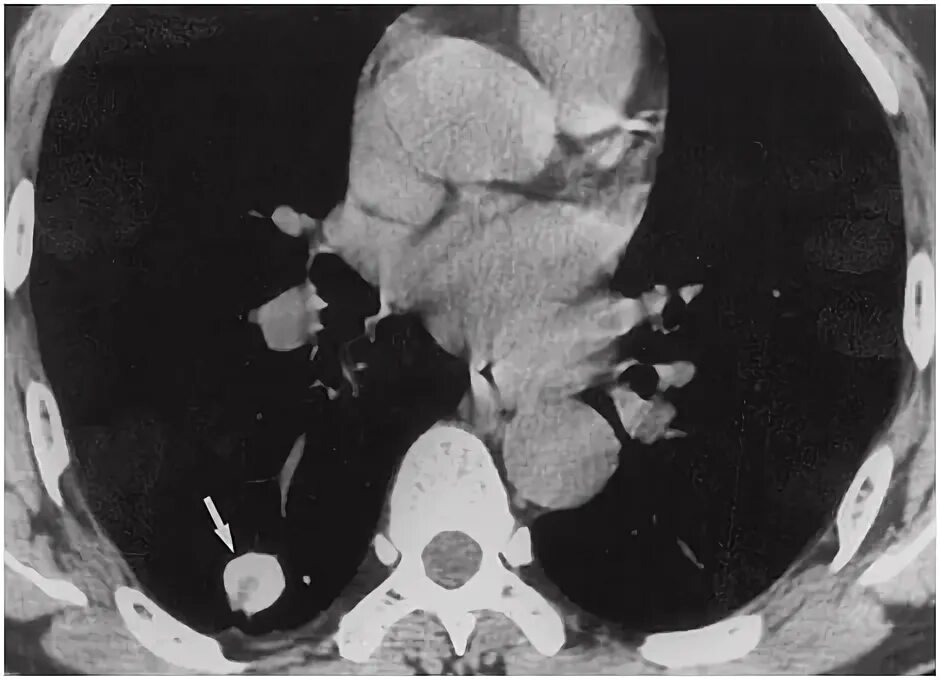

Метатуберкулезные изменения в легких что это означает